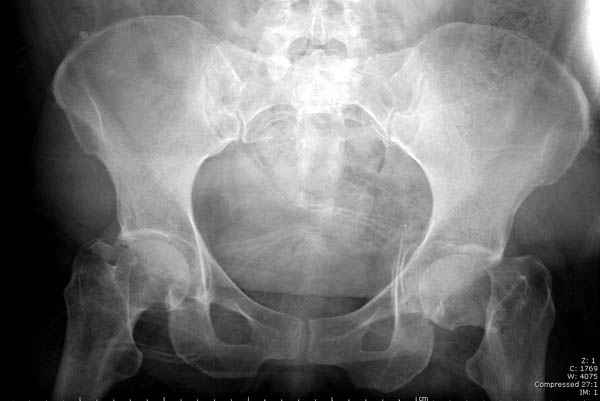

Мы сейчас наблюдаем больную с похожим состоянием, больной 54, после

автоаварии, со множественными

переломами скелета.

Состояние осложнена черепномозговой и абдоминальной травмой, переломы

L2-5, челюстно-лицевые переломы и состояние после транспланта почки.

Удаление селезенки при поступлении, была нестабильная, в данное время

приходит в сознании, находилась в реанимации, перевели в общую палату.

Перелом шейки смогли зафиксировать через пару дней, ацетабулум до сих

пор не оперирован, на вытяжении.

Из-за упущенного времени (три недели с момента

поступления) ацетабулум ведем консервативно.

Вложение не в текстовом формате было извлечено…

Имя     : 5 fem neck CRM.jpg

Тип     : image/jpeg

Размер  : 18998 байтов